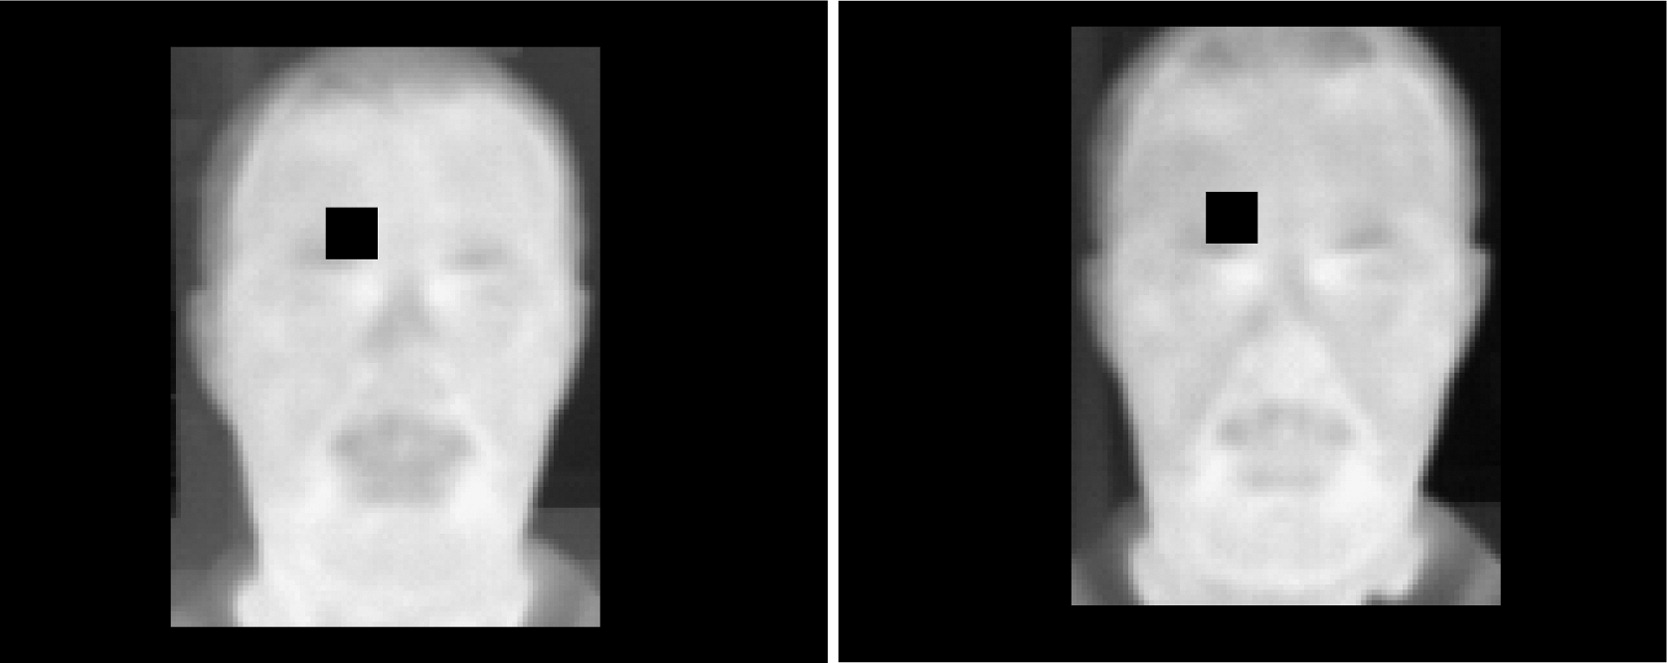

Koukiou and Anastassopoulos/Forensic Science International, 2015

Next the researchers had artificial neural networks compare the sober versus drunken faces, one pixel at a time. They found that the best indicator of a person’s state of intoxication is the temperature of the forehead and nose. Using that information, they built an algorithm that could determine who was sober and who was drunk with a 90 percent accuracy, even on faces that it hadn’t been trained on, and even if it didn’t know what the person looked like sober.